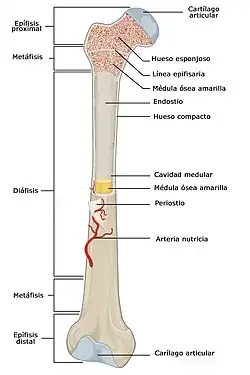

Los huesos que forman el esqueleto constan de varias partes:[2]

- Diáfisis. Se llama diáfisis a la porción central o cuerpo de los huesos largos.[3]

- Epífisis. Se llama epífisis a cada uno de los extremos de los huesos largos.

- Metáfisis. Se llama metáfisis a una zona intermedia de los huesos largos que está situada entre la zona central (diáfisis) y los extremos (epífisis).

- Cartílago articular. Es una estructura formada por tejido cartilaginoso que se interpone entre los extremos de dos huesos adyacentes, permitiendo el deslizamiento de las superficies en contacto gracias a que presenta un coeficiente de fricción muy bajo. No tiene vasos sanguíneos y se nutre a través de las moléculas del líquido sinovial que penetran en su superficie. Está formado por células especializadas llamadas condrocitos y una matriz extracelular compuesta por fibras de colágeno tipo II.[4]

- Periostio. Membrana de tejido conectivo fibrosa y resistente que cubre los huesos por su superficie externa.

- Cavidad medular. Es un espacio sin tejido óseo ubicado en la zona central de la diáfisis de los huesos largos. La cavidad medular esta rellena por médula ósea amarilla, tejido formado por células adiposas que almacenan importantes cantidades de triglicéridos que suponen una reserva energética. No debe confundirse la médula ósea amarilla con la médula ósea roja, también presente en los huesos, que tiene la función de producir las células sanguíneas.

- Endostio. Membrana delgada del tejido conjuntivo que tapiza la superficie interior de la cavidad medular de los huesos largos.[5][6]

- Arteria nutricia. El hueso necesita sangre que le aporte a sus células oxígeno y nutrientes. Por ello cada hueso esta irrigado por una arteria nutricia que penetra en su estructura a través de un pequeño orificio llamado agujero nutricio, una vez en el interior se divide en ramas progresivamente más pequeñas que se distribuyen por todas las áreas del hueso.